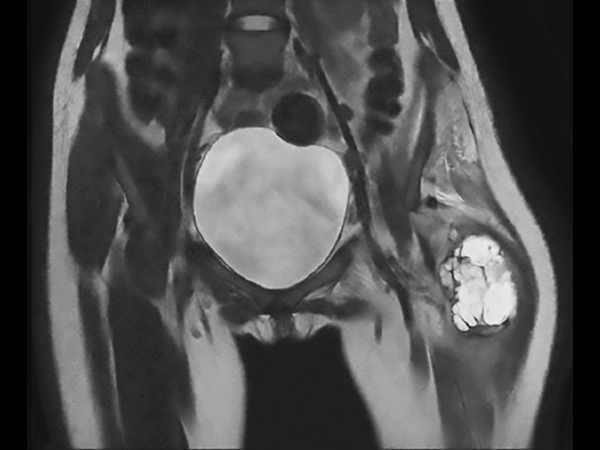

Preoperative MRI in this young girl demonstrates the large tumor with a necrotic component and areas of fluid. The tumor extends down into proximal part of femur. Edema is seen along the femoral shaft down to the knee and in the gluteal muscle. T2W mDIXON TSE in-phase and water images show the superb fat suppression of mDIXON TSE. The two-station MobiView also demonstrates the high quality mDIXON TSE fat suppression over large region and both images with and without fast suppression are obtained in about half the time needed for conventional scans.

Coronal T2w TSE mDIXON (in-phase, MobiView)